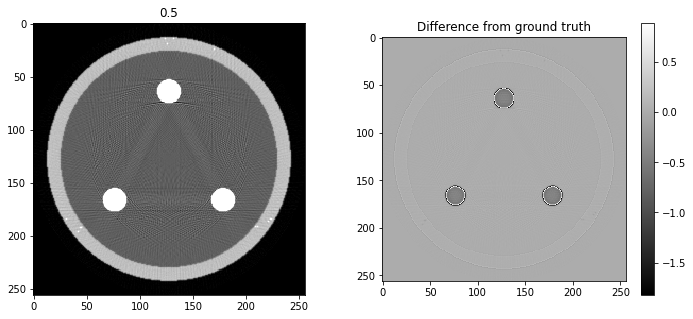

# Question 12

search = np.linspace(0,1,11)

for alpha in search:

rec = out+alpha*reproj

f,ax = plt.subplots(1,2,figsize=(12,5))

ax[0].imshow(rec,vmin=0,vmax=0.5)

ax[0].set_title(alpha)

im = ax[1].imshow(img[80]-rec)

f.colorbar(im,ax=ax[1])

ax[1].set_title('Difference from ground truth')

plt.show()